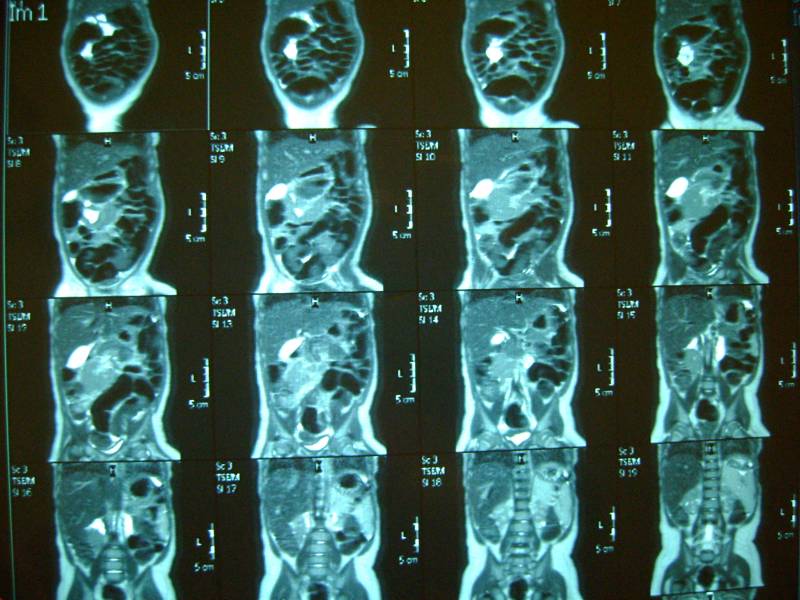

еще